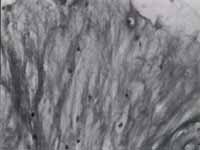

Fig. 2: Sinovitis crónica (rodilla).

Fig. 3: Cambios en la orientación de las fibras